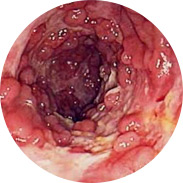

Inflamația și supurația mucoasei rectale

Sângerarea poate duce la apariția anemiei

O creștere a temperaturii corpului, cu inflamație severă, poate duce la febră

Și cel mai rău lucru este cancerul rectal!Studiile clinice pe scară largă ale Proctolax au fost efectuate la Centrul Medical Român (București) în 2016. În total, mai mult de 1000 de bărbați și femei cu hemoroizi de diferite grade au participat la studii. Toți subiecții au folosit crema Proctolax timp de 3 săptămâni. Chiar și medicii au fost uimiți de rezultatele studiului!